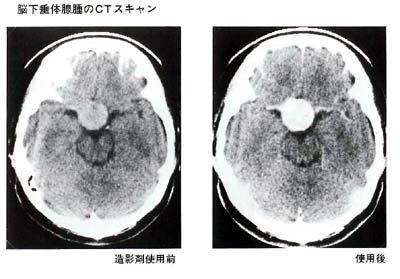

(2)CTスキャン

(1)は脳下垂体を包んでいる骨の変化を調べるもので、いわば腺腫の間接的な診断にすぎません。

一方、CTスキャンは腺腫自体を描出出来ますので、その正確な大きさと拡がりを知ることが可能です。造影剤を点滴する前と後とで2回検査を行ない、その差を調べます。この際、まれに造影剤によってじんましん等アレルギー症状を示す方がいます。